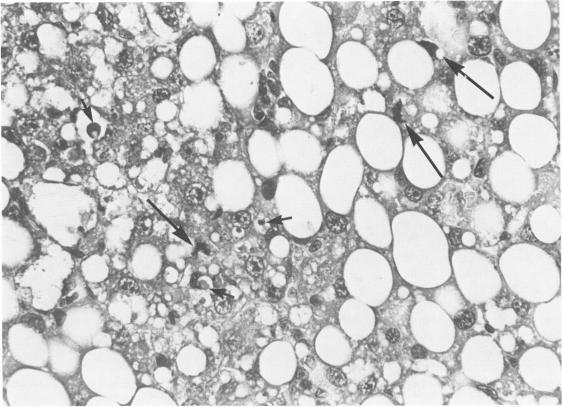

This study was undertaken to test the hypothesis that the basis for the cell proliferation seen in the livers of rats fed a choline-deficient methionine-low (CMD) diet is regeneration following hepatocyte cell death and necrosis. Exposure of rats to a CMD diet for 2 weeks was found to induce liver cell loss and necrosis as monitored by three different approaches: 1) histologic examination, 2) serum sorbitol dehydrogenase assay, and 3) measurement of the total radioactivity in liver DNA prelabeled during a prior period of regeneration. These observations suggest that the basis for liver cell proliferation in rats fed a CMD diet probably resides in the cell loss and necrosis induced in the liver by the deficient diet.